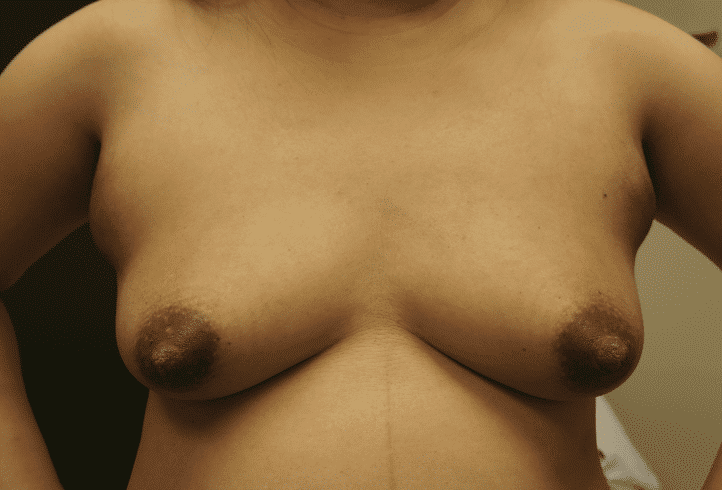

Gestational gigantomastia likely represents a spectrum of excessive breast growth during pregnancy. It may include women who grow multiple cup sizes, or those for whom the breast growth is so significant it can cause mobility impairments. Hormonal factors may play a role in gigantomastia, but true cause remains unknown. It also remains unclear whether the growth represents true glandular development or simply fluid retention in the breast as occurs in other parts of the body during pregnancy. Women gigantomastia that is not significant enough to cause skin breakdown but do experience growth do not necessarily produce large volumes of milk.

Photo: Clara Farley

During pregnancy, it is treated by bromocriptine (an anti-prolactin agent) alternating with metformin (modulates insulin). Postpartum, patients should be given bromocriptine or cabergoline (anti-prolactin agent) before lactogenesis II (secretory activation, or “milk coming in”) to reduce the risk of skin necrosis (ulceration and death of skin). Donor milk or formula supplementation should be planned. Patients can later undergo elective breast reduction. The patient above is pictured below at end of pregnancy after being treated with lymphatic drainage and bromocriptine during pregnancy:

Improvement in lymphedema with lymphatic drainage and supportive bra/garment, just before delivery. Photo: Clara Farley, MD

As discussed in the Pregnancy and Birth section, women may experience breast lymphedema (swollen breast) and pain, particularly during periods of early breast growth in the first trimester and in the last trimester nearing childbirth. This is more common than true gigantomastia. This discomfort is related to increase in the gland, blood vessels, and surrounding fluid. Swelling and even pitting usually is most evident in the lower part of the breast, and can be pink or mildly reddish in color. These cases also. can gain significant relief from lymphatic massage and supportive bras. Any asymmetry in presentation warrants referral to a breast surgeon to evaluate for breast masses and/or inflammatory breast cancer.